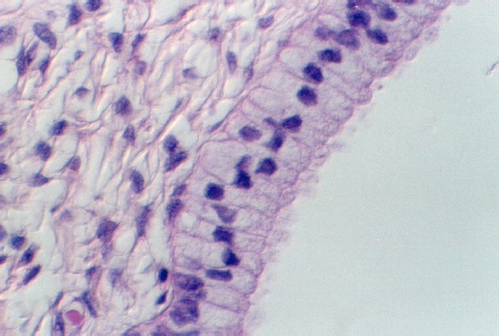

Slide 86 shows a uterus in the proliferative phase. The endometrium is illustrated in the photograph below. Note that the cells are low columnar to high columnar. The glands are relatively straight with a narrow lumina. Outside the glands is the highly cellular lamina propria. The following photos illustrate the proliferative phase with higher magnifications.

After ovulation, the uterine lining becomes more tortuous. The lining is now under the control of progesterone. This steroid hormone stimulates the lining to secrete material that may help nourish both sperm and a potential pregnancy. The glands expand and the lumina are wide and contain products of secretion. The glandular epithelium may be characterized by a droplet of secretory material under the nucleus (near the base) about 2 days after ovulation (day 16). Then, the secretory products move more towards the lumen. Slide 87 shows the Secretory phase of the uterine lining. Note the sections showing coiled or tortuous glands and the dense lamina propria.